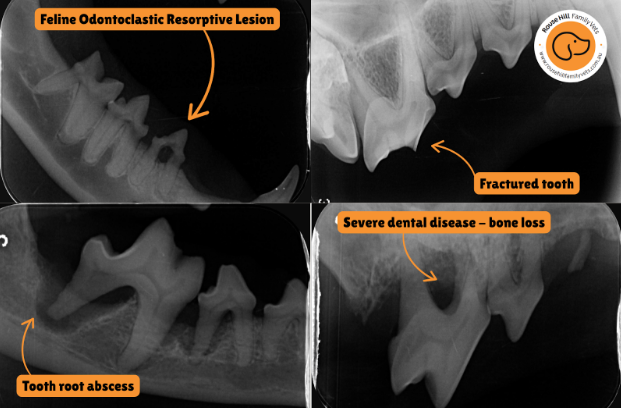

📸 A real example: what we found under the surface

This is an actual dental X-ray from one of our patients. From the outside, this tooth looked concerning — but the X-ray confirmed severe bone loss around the roots, and infection that had been brewing deep inside the jaw.

Without X-rays, this pet would have gone home with pain, infection, and worsening dental disease.

With them? We could treat the problem at its root (literally) — and get them back to living pain-free.